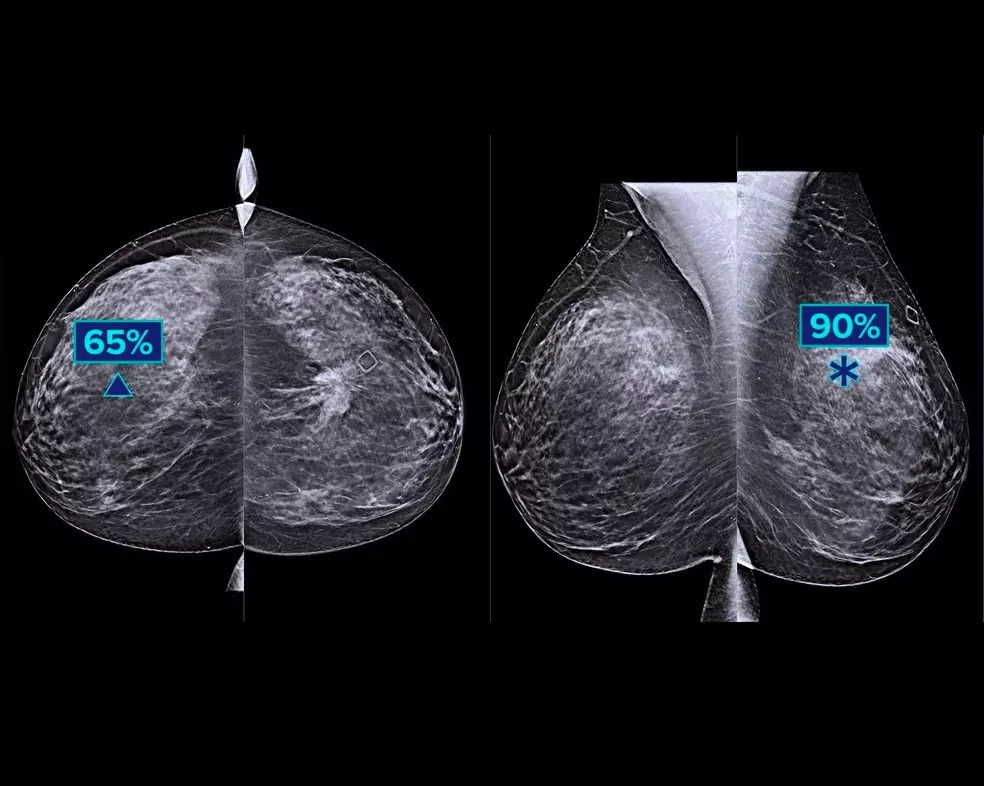

En djupinlärningsalgoritm utformad för att underlätta radiologers diagnostiska arbete och detektera bröstcancer1–3 från tomosyntesbilder från Hologic Dimensions Mammography® Systems. Algoritmen lokaliserar lesioner som troligtvis är bröstcancer genom att söka i varje snitt i uppsättningen av tomosyntesbilder. De misstänkta områdena markeras för samtidig granskning vid radiologens arbetsstation för att underlätta tolkning.

Algoritmen letar efter tre huvudgrupper av misstänkta lesioner: förkalkningar, resistenser, tätheter och distorsioner samt en kombination av dessa lesioner. Resultaten kan variera på olika arbetsstationer för granskning.

Genom integrering på arbetsstationen för bildtagning kan högriskfall flaggas för omedelbar granskning. Ger mätvärden på fallnivå, vilket hjälper till att kategorisera fall för prioritetsgranskning.